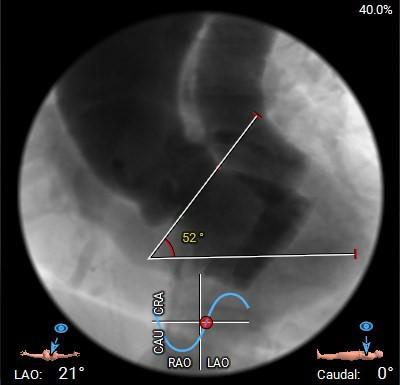

瓣环角度及弓角弓距

◇ 主动脉瓣环水平夹角52°,非横位心,主动脉弓角度较锐(43°)及弓距偏短;